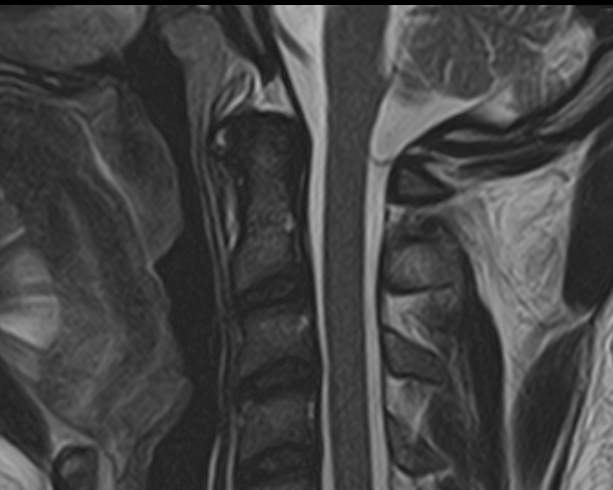

Магнитно-резонансная томография показывает состояние позвонков и связок краниовертебрального отдела, в том числе последствия застарелых травм. А также отклонения в строении:

Краниовертебральный переход − это место соединения черепа с шейным отделом позвоночника. МРТ краниовертебрального перехода делают с целью изучения всех его структур:

Краниовертебральные аномалии (КВА) представляют собой нарушения анатомического взаиморасположения структур позвоночника и черепной коробки. Часто эти патологии протекают бессимптомно, и человек может жить годами, не догадываясь о сбоях в работе организма. Со временем болезнь переходит в хроническую стадию и провоцирует поражения позвоночной артерии, сдавление ствола или корешка спинного мозга, повышение внутричерепного давления. Особенно опасны отклонения в устройстве краниовертебрального перехода у маленьких детей, у которых они могут вызвать расстройства дыхания.Краниовертебральный переход состоит из основания черепа и первых 2 шейных позвонков. Нарушения правильности его строения негативно отражается на работе головного и спинного мозга, что приводит к неврологическим проблемам. Очень важно вовремя выявить патологии зоны соединения позвоночного столба и неподвижной части черепа, если пациенту предстоит мануальная терапия или оперативное вмешательство.В этом случае показана МРТ зоны краниовертебрального перехода, которая основана на принципе использования высокочастотного магнитного поля и радиочастотных импульсов. На данный момент это наиболее информативный и безопасный метод диагностики. Он отличается неинвазивностью и отсутствием лучевой нагрузки, и при этом позволяет получать детализированные трехмерные снимки изучаемой области.